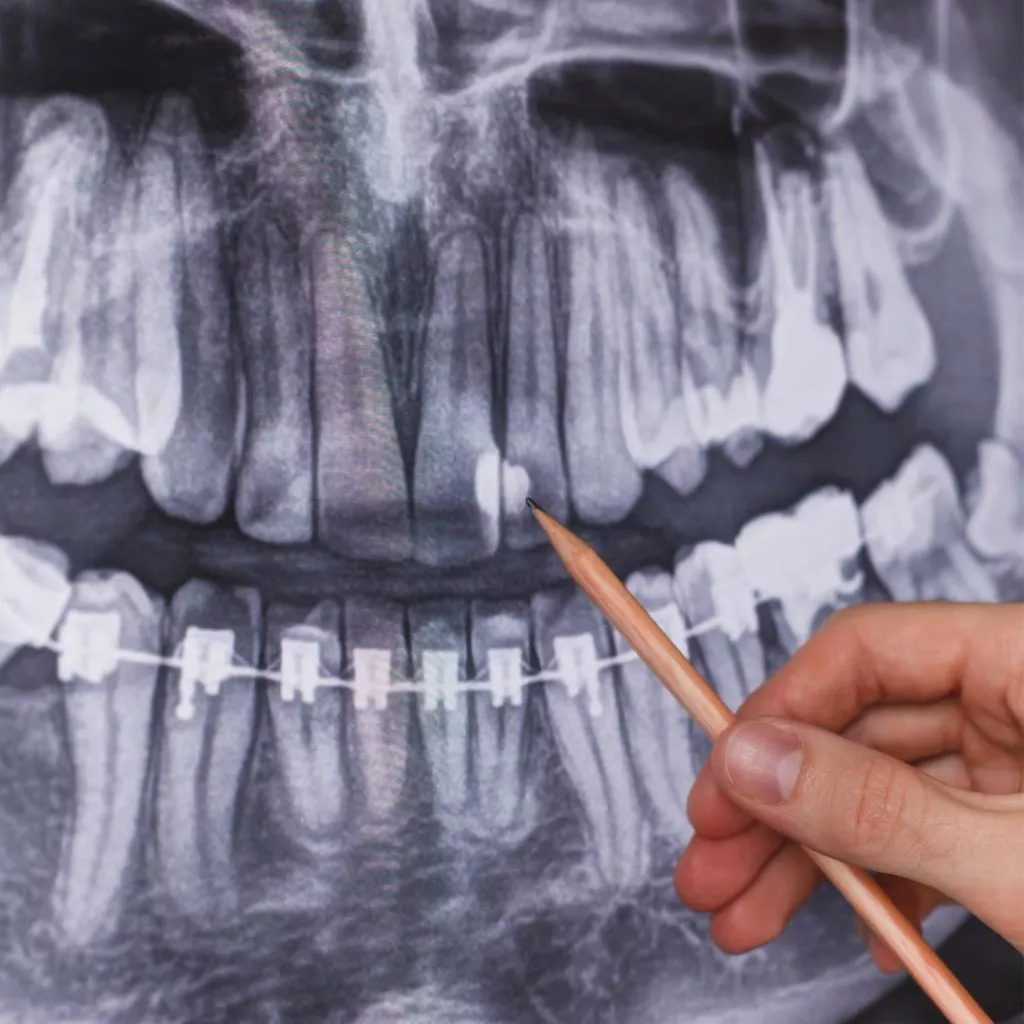

At Channel Islands Family Dental, we use cutting-edge intraoral dental imaging to deliver precise and detailed evaluations of your oral health. This advanced technology enables us to capture high-quality images of your teeth and gums, allowing for accurate and personalized treatment plans. Visit our locations in Oxnard, Santa Paula, Ventura, Newbury Park, and Port Hueneme to discover how intraoral dental imaging can improve your dental care experience.